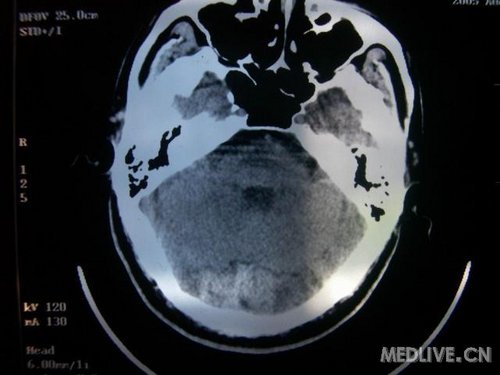

病人男性 73岁 市民 以“幻听、幻视两天,言语含糊、精神错乱一天”入院。

两天前无诱因出现幻听、幻视,描素眼前有彩色的圆圈,听见有人说话(但说什么不详),一天前出现胡言乱语,言语含糊,精神错乱,问话不答,行走略有不稳,来我院就诊,门诊头CT检查:(下面有片)入院后查体不合作,表情淡漠,问话不答,大致检查了一下,颅神经未见明显异常,颈软,右手活动似忽略差。其他检查不配合。脑电图:广泛轻-中度异常。

既往史:半年前曾患“右侧脑梗塞”但无明显后遗症,生活能自理,无高血压、糖尿病、心脏病史。

此次入院时的片子: